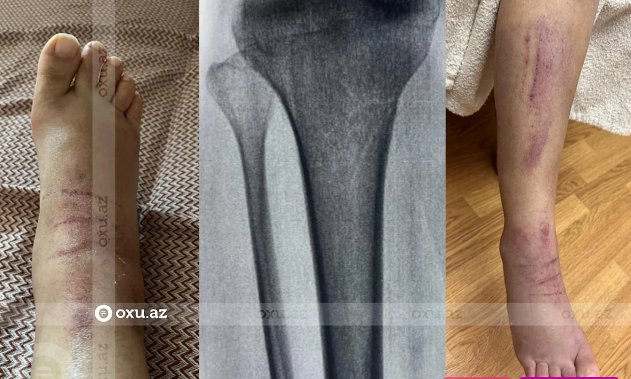

"Yoldaşım və biri səkkiz, digəri iki yaşında olan iki övladım yolu keçərkən piyada zolağının üstündə onları "Avromed" şirkətinə məxsus avtomobili etibarnamə ilə idarə edən sürücü Afiq Rafiq oğlu Abışov vurub. Qəza nəticəsində yoldaşım və böyük oğlum xəsarət alıblar. Hadisə yerinə gələrək sürücü ilə birlikdə onları xəstəxanaya çatdırmışam, lazımi müayinələr aparılıb və yoldaşımın ayağında, dizdən aşağı hissədə sınıq olduğu müəyyən olunub.

Qəzanı törədən şəxs həmin gün xəstəxana xərclərini çəkdi, həkim də onun yanında sümükdə prosesin necə getdiyini müəyyən etmək üçün on gündən bir müayinəyə gəlmək lazım olduğunu bildirdi.